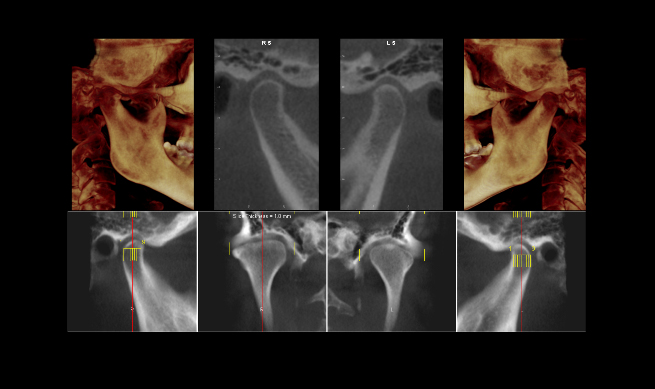

Diagnóstico Para Disfunção Temporomandibular

A tecnologia está a nosso favor! Com sua evolução conseguimos ter um estudo de imagens das Articulações Temporomandibulares e estruturas circunvizinhas. A tomografia computadorizada nos permite avaliar as estruturas ósseas e a Ressonância Magnética nos permite avaliar as estruturas musculares, áreas de inflamação dentro da cápsula articular e principalmente visualizar o disco articular, sua forma … Continue lendo Diagnóstico Para Disfunção Temporomandibular